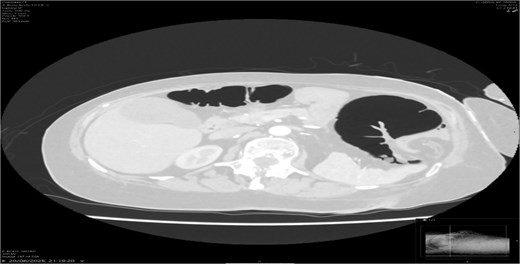

A contrast-enhanced CT scan of the abdomen demonstrated a whirl sign at the mesenteric root (Figs 1 and 2), dilated transverse colon with a transition point at the splenic flexure (Fig. 3), and no evidence of ischemia or perforation (Fig. 4). These findings were consistent with TCV.

Axial CT showing dilated transverse colon at the splenic flexure.

Radiology plays a crucial role; plain abdominal radiographs may show nonspecific distension but rarely establish the diagnosis. A CT scan is the gold standard [8], with the whirl sign, transition point, and proximal dilatation being diagnostic. CT also assesses complications such as ischemia and perforation, which carry high mortality [9].